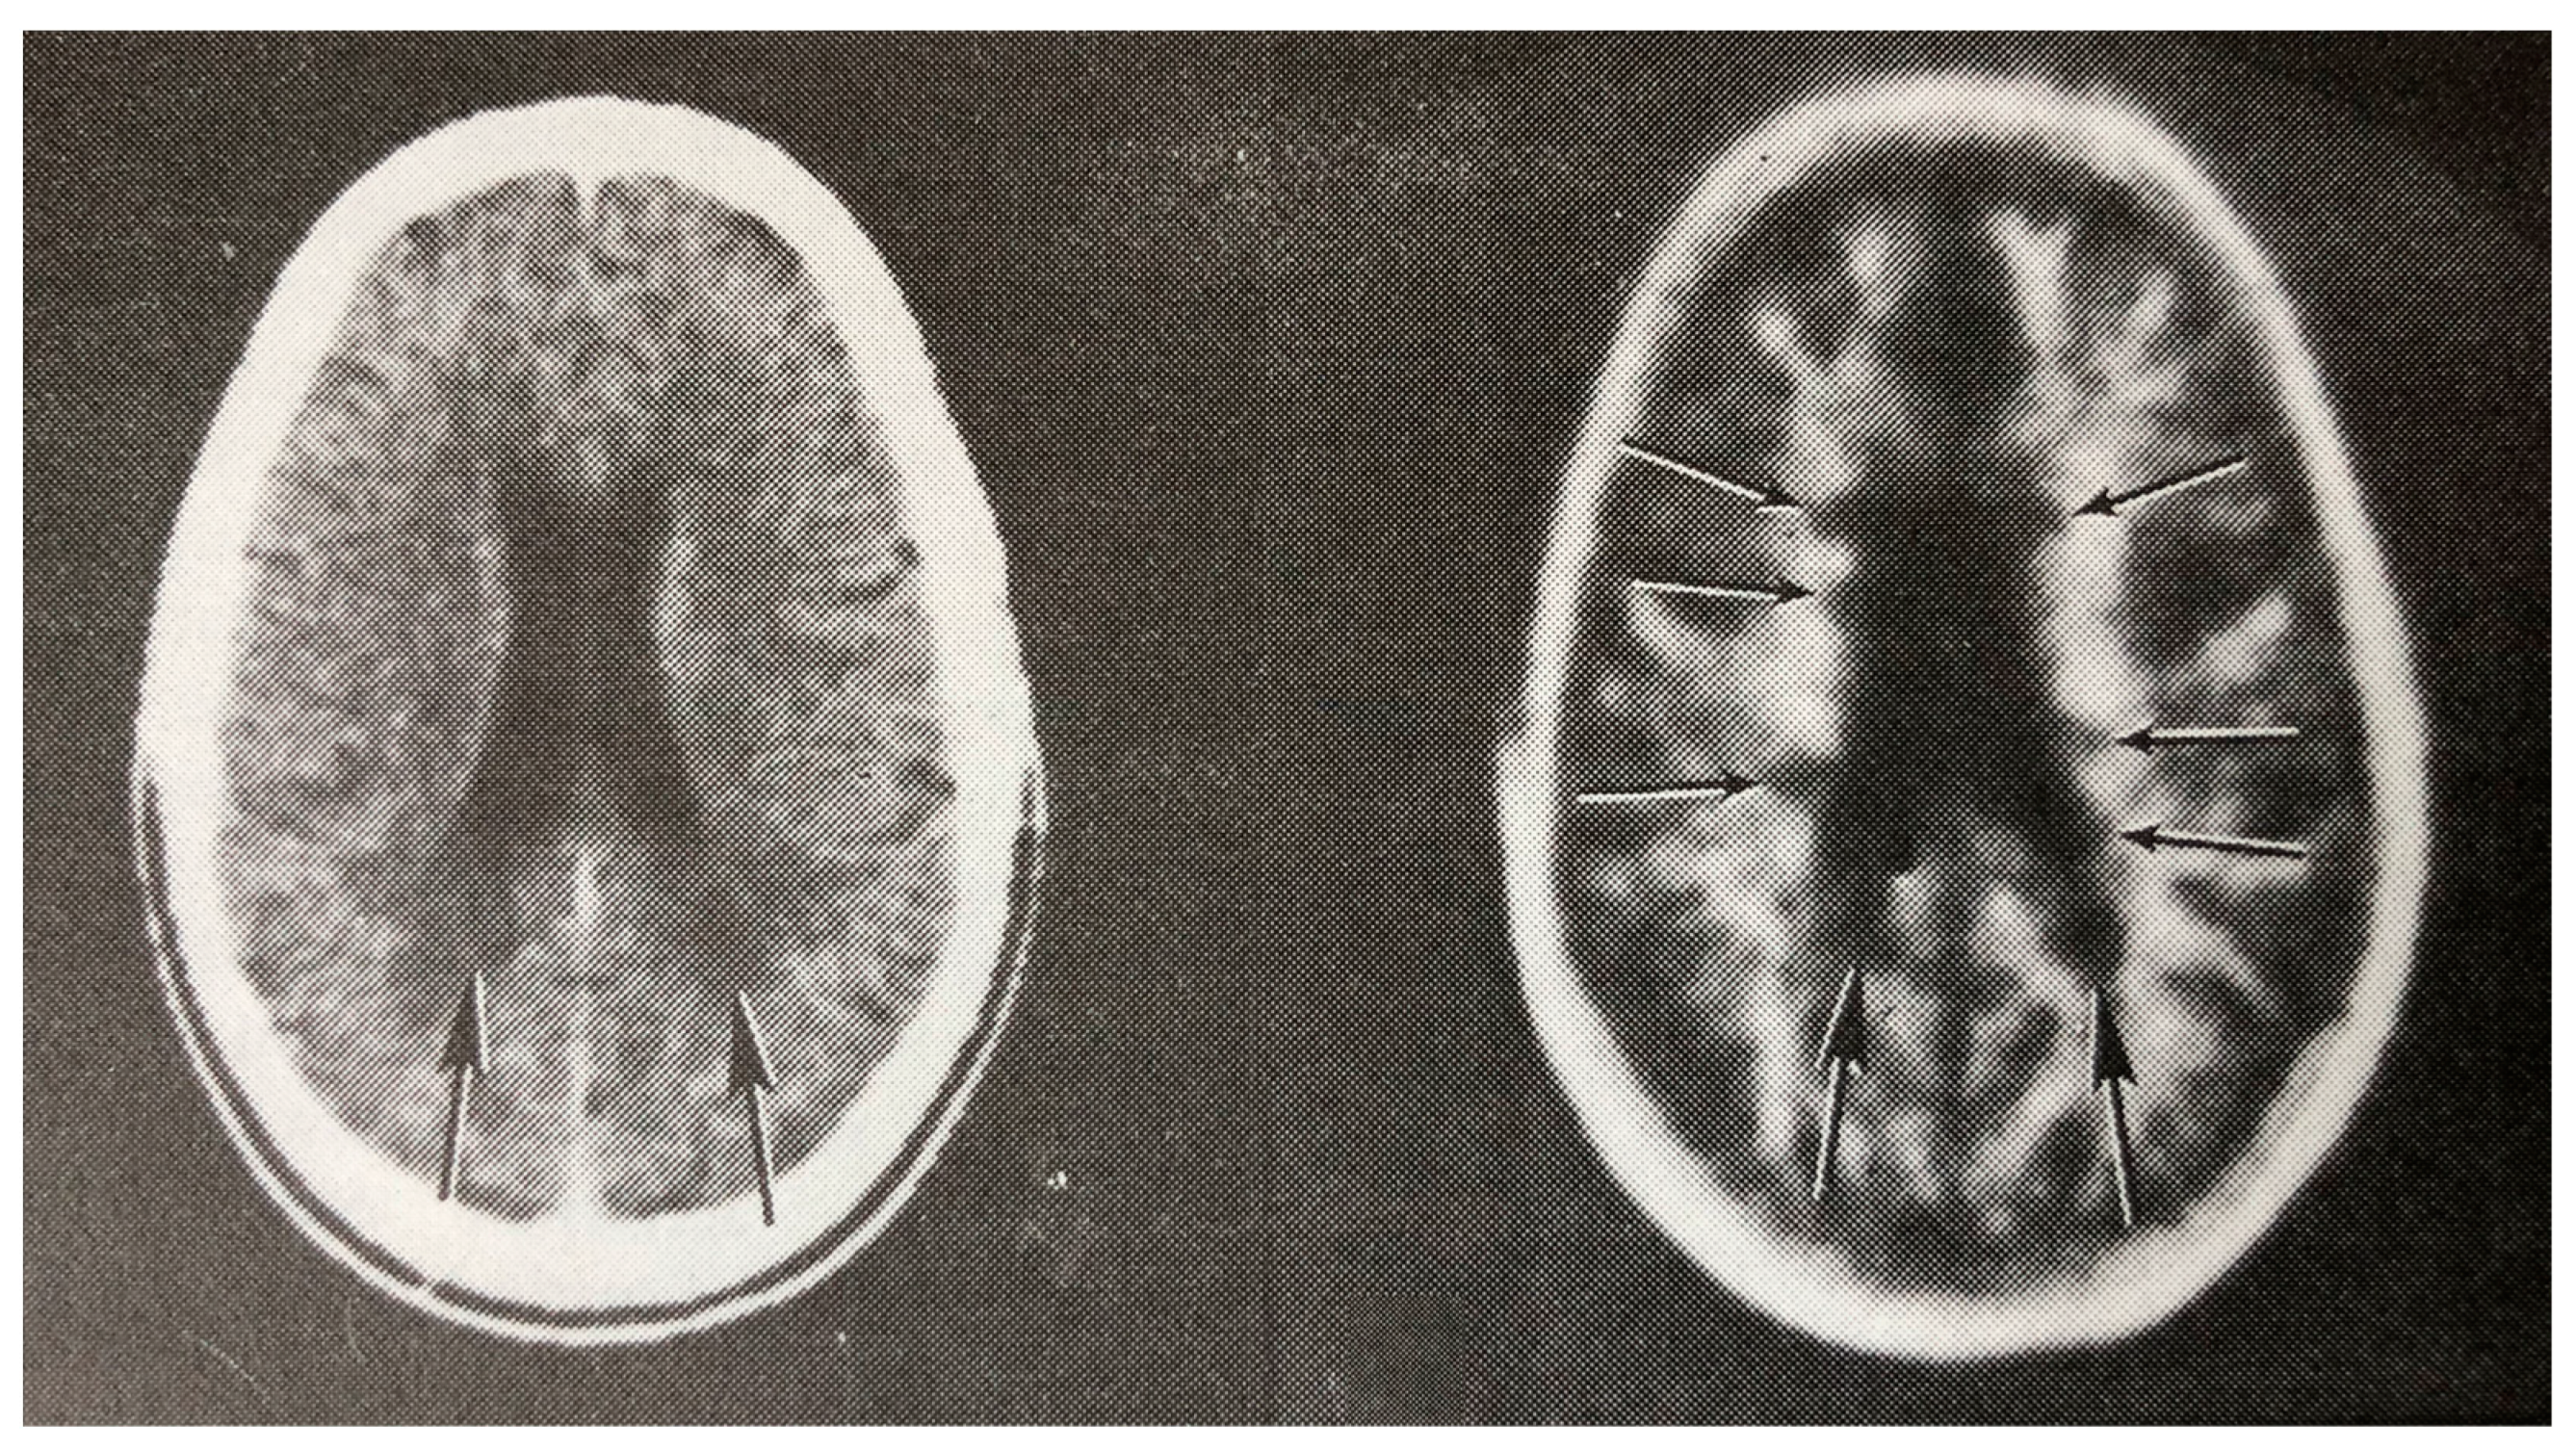

Figure 7.

Multiple sclerosis (MS): CT (left) and inversion recovery (IR) (right) (November 1981) [7]. Two larger lesions are seen on the CT image (left, arrows). These are also seen on the IR image (right, arrows). There are an additional six lesions seen in the periventricular white matter on the IR image (arrows). The additional lesions are seen in normal appearing white matter on the CT image.

Multiple sclerosis (MS): CT (A), inversion recovery (IR) (B) and long TR, long TE spin echo (SE) (C) (July 1982) [8]. A single MS lesion is seen on the CT image (arrow) (A). This is also seen on the IR and SE images (arrows). There are an additional four lesions seen on the SE image (C) in normal appearing white matter on the CT image (A).